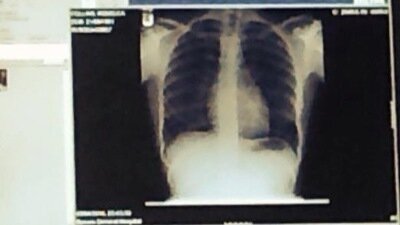

I was first diagnosed with a PE on my lung in 2014 (photo is my actual lung with dark spot which is the clot) which was caused by the oestrogen pill. Nobody warned me, nobody told me I could potentially suffer one, nobody told me they can be fatal, I didn’t know what they were, it is not hereditary in my family.